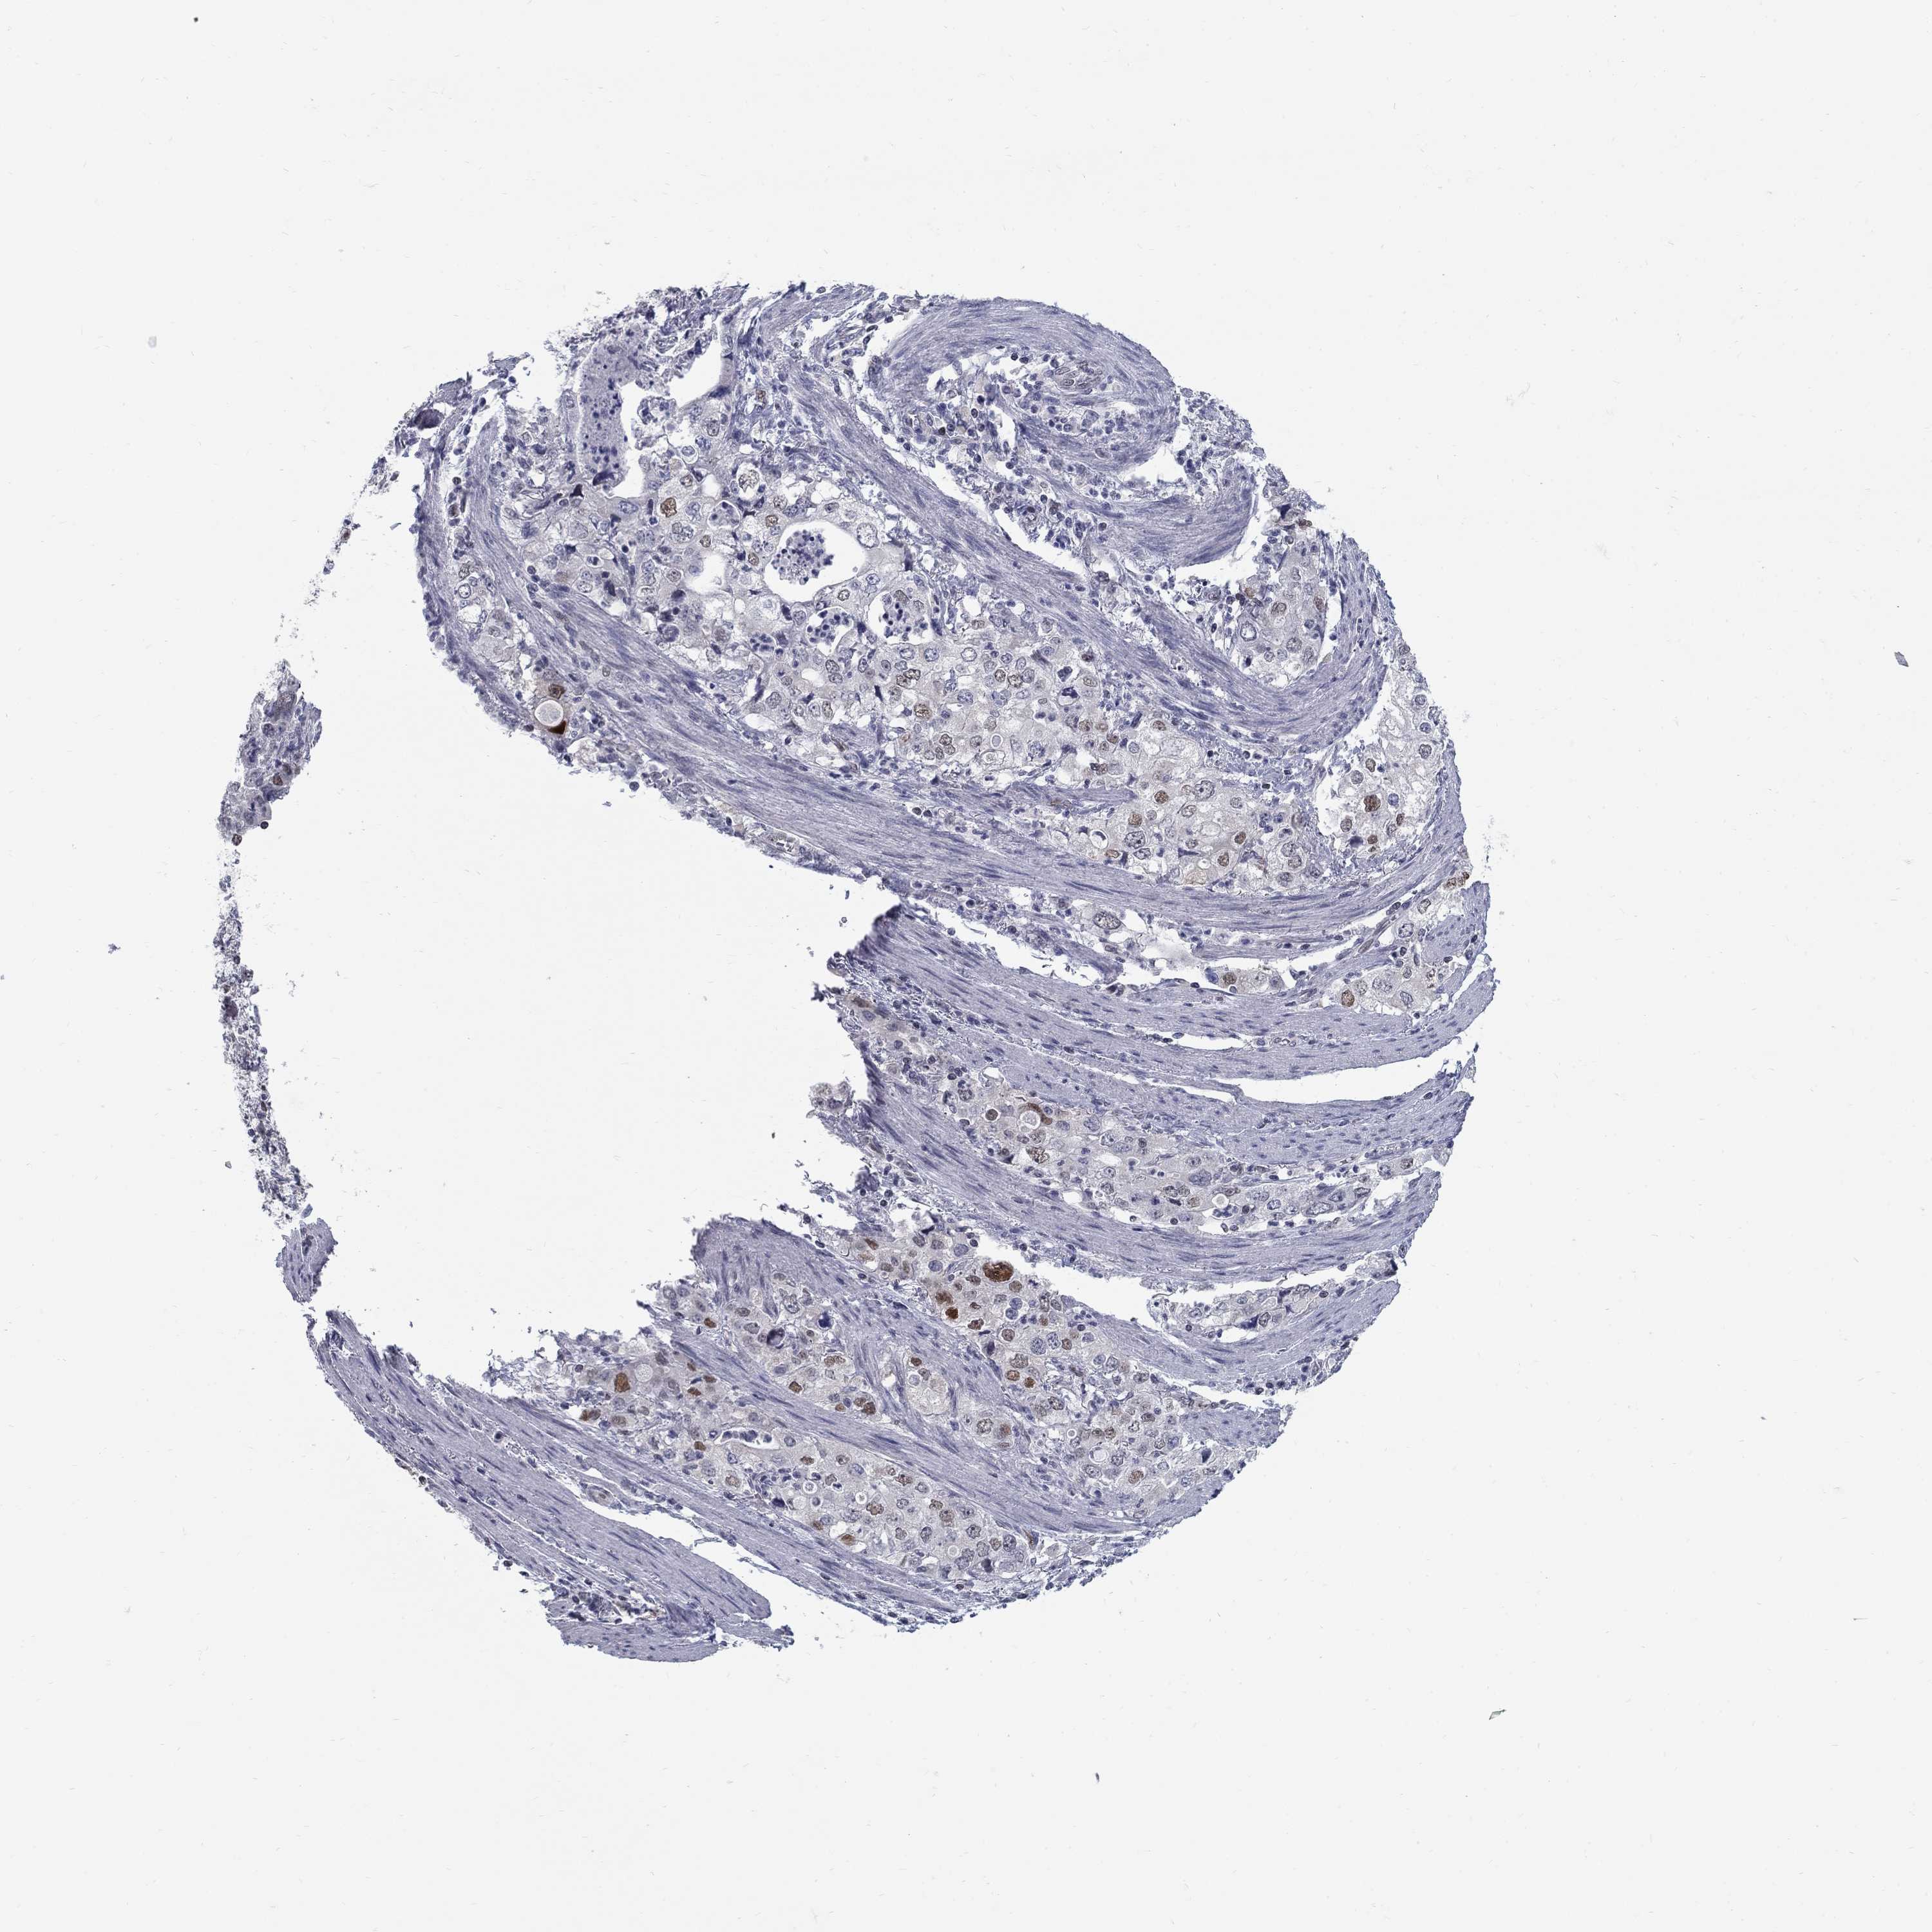

STOMACH CANCER - Protein expressioni

A mouse-over function shows sample information and annotation data. Click on an image to view it in a full screen mode. Samples can be filtered based on level of antibody staining by selecting one or several of the following categories: high, medium, low and not detected. The assay and annotation is described here.

Note that samples used for immunohistochemistry by the Human Protein Atlas do not correspond to samples in the TCGA dataset.

Antibody stainingi

Antibody staining in the annotated cell types in the current human tissue is reported as not detected, low, medium, or high, based on conventional immunohistochemistry profiling in selected tissues. This score is based on the combination of the staining intensity and fraction of stained cells.

Each image is clickable and will lead to virtual microscopy that enables deeper exploration of all samples and also displays staining intensity scores, fraction scores and subcellular localization as well as patient and tissue information for each sample.

Antibody HPA077882

Staining

High

Medium

Low

Not detected

Intensity

Strong

Moderate

Weak

Negative

Quantity

>75%

75%-25%

<25%

None

Location

Nuclear

Cytoplasmic/membranous

Cytoplasmic/membranous,nuclear

Adenocarcinoma, NOS